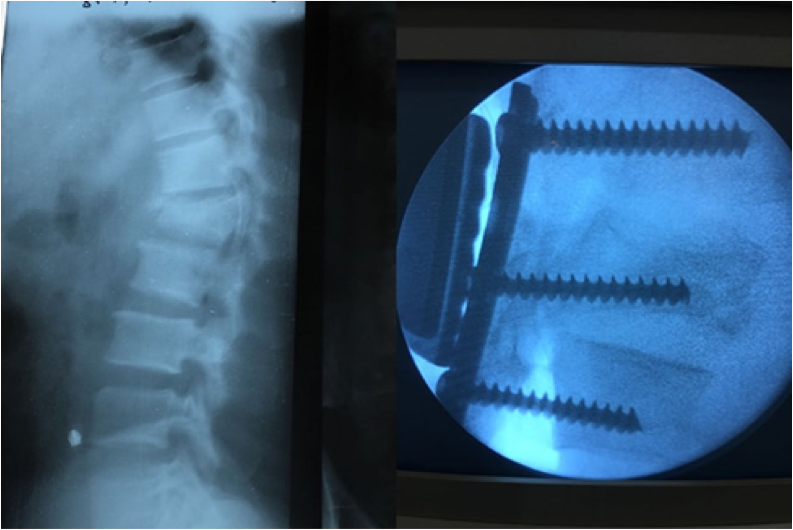

Venimos anunciando nuestra intención de iniciar la cirugía de la columna vertebral en 2018.

La ocasión se presentó con un paciente que tenía una grave fractura vertebral con una parálisis en miembro inferior. El Dr. Areta tuvo el coraje de operarle con los materiales de los que disponemos (actualmente no específicos para la cirugía de raquis) con un fantástico resultado y con una progresiva recuperación de la movilidad y fuerza muscular en su pierna paralizada.